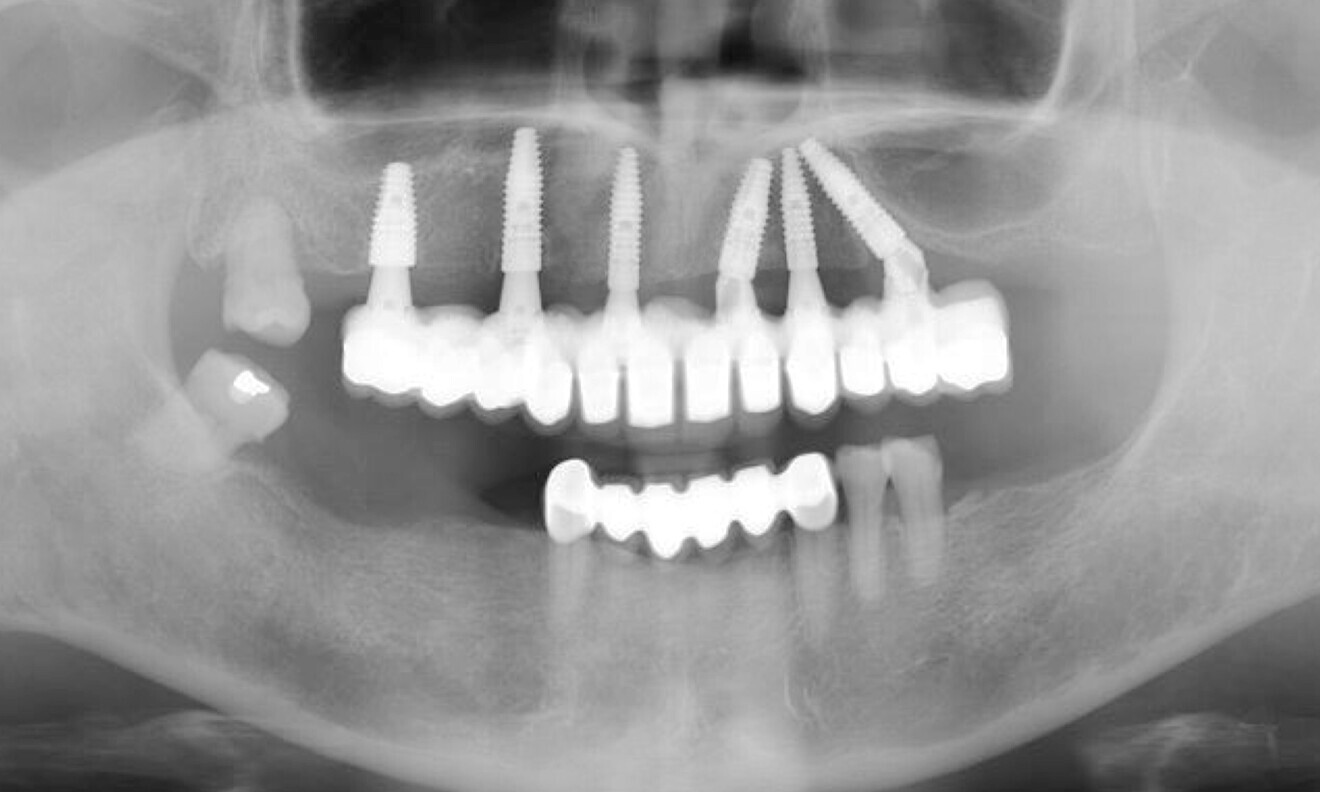

The extra-oral examination showed a low smile line, and the intra-oral examination found a removable bridge from tooth #13 to tooth #23 that was poorly adapted and showed signs of deterioration. The maxillary teeth, with the exception of tooth #18, were mobile. Generalised gingival inflammation, bleeding on probing and dental caries were also present (Fig. 1). The radiographic examination exposed severe bone loss in the posterior of the maxillary left quadrant, as well as caries and apical lesions on maxillary teeth (Fig. 2).

After conducting both radiographic and clinical assessments, the patient was categorised as having a complex condition according to both the surgical and prosthodontic SAC classifications. This classification system, developed by the International Team for Implantology, assists in evaluating the level of challenge and potential complications linked to implant-related restoration (Fig. 3).